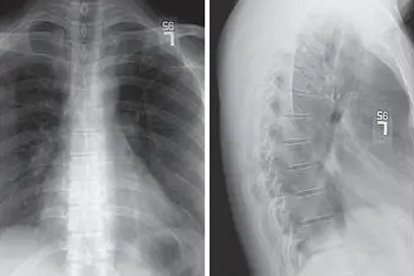

胸椎狭窄是什么原因引起的

胸椎狭窄可能由胸椎间盘突出、胸椎韧带骨化、胸椎退行性变、胸椎外伤、先天性椎管发育异常等原因引起,通常表现为胸背部疼痛、下肢麻木无力、行走不稳等症状。胸椎狭窄可通过药物治疗、物理治疗、手术治疗等方式改善。